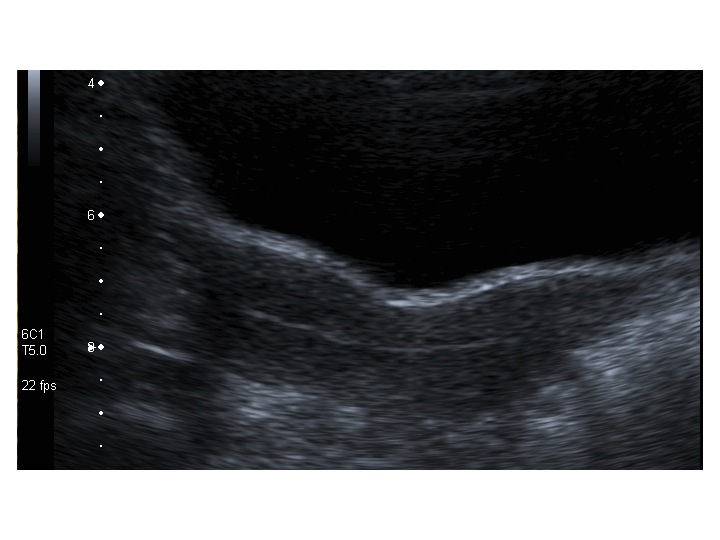

All’ecografia pelvica si osservano le ovaie a “banderella” (figura) e il cariotipo rivela l’assenza di un cromosoma X o la presenza di un mosaicismo, 45 X0/46XX nella forma più comune; nel 5% dei casi di ST può essere presente un frammento di cromosoma Y.

Dopo l'induzione di pubertà è ben visibile la rima endometriale (nella paziente 2 era appena accennata anche nelle immagini pre-terapia), soprattutto nelle sezioni longitudinali, con l'assenza di follicoli a livello ovarico